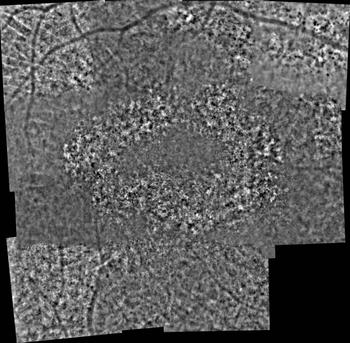

Structural photoreceptor abnormalities and an area of central sparing found.

Investigators corroborate the hypothesis that retinal ganglion cells with dendrites stratified in the off sublaminae could be damaged.